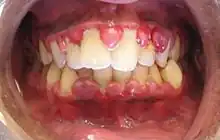

Gingivitis is a non-destructive disease that causes inflammation of the gums;[1] ulitis is an alternative term.[2] The most common form of gingivitis, and the most common form of periodontal disease overall, is in response to bacterial biofilms (also called plaque) that are attached to tooth surfaces, termed plaque-induced gingivitis. Most forms of gingivitis are plaque-induced.[3]

The symptoms of gingivitis are somewhat non-specific and manifest in the gum tissue as the classic signs of inflammation:

- Swollen gums

- Bright red gums

- Gums that are tender or painful to the touch

- Bleeding gums or bleeding after brushing and/or flossing

- Bad breath (halitosis)

Additionally, the stippling that normally exists in the gum tissue of some individuals will often disappear and the gums may appear shiny when the gum tissue becomes swollen and stretched over the inflamed underlying connective tissue. The accumulation may also emit an unpleasant odor. When the gingiva are swollen, the epithelial lining of the gingival crevice becomes ulcerated and the gums will bleed more easily with even gentle brushing, and especially when flossing.